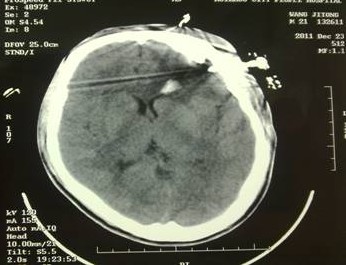

于是家属慕名求助于我院余永强主任,在伤后第三天转来我院。余永强主任主持术前讨论,决定为患者施行微创手术清除血肿。通过CT扫描进行术前精确定位,随后在局麻下进行微创手术。术中利用余主任设计研制的“e形微创手术定向仪”作引导,将穿刺针准确无误置入血肿靶心,顺利地清除了绝大部分血肿。术后复查头颅CT,血肿清除超过90%(图2)。凭借微创技术,头皮仅仅只需要一个直径3毫米的小孔,通过一根高科技微创穿刺针,便可达到同样的甚至更好的治疗效果(图3)。术后留置引流1天,第7天即痊愈出院。手术达到近乎“完美”的效果!患者亲属大为感慨微创手术的“神奇”,术后专程送来锦旗一幅――“微创手术显神功” !(图4)

图2(1):术后立即复查CT,血肿清除90%以上,穿刺针定位精确,

无损伤出血;